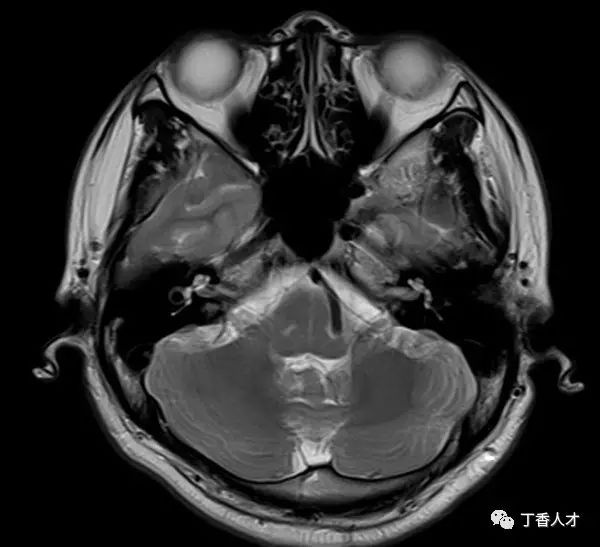

摸摸人家的头,全方位的。人家也不反对我,以为我在按摩。我一边摸一边想,他的大好头颅啊真是奇形怪状,CT 或者 MRI 断面会是什么样子呢?